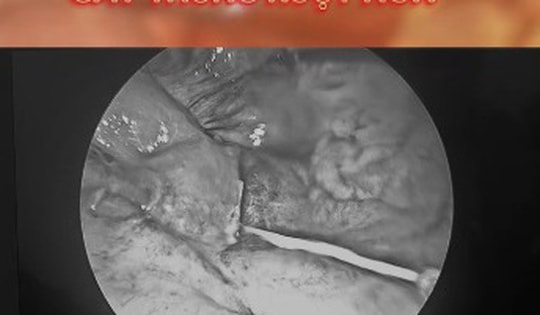

Cứu sống một ngư dân bị xương cá đâm thủng ruột

PLBĐ - Bệnh viện Quân y 175 đã tiếp nhận nam bệnh nhân là ngư dân tàu cá được chuyển từ Trung tâm Y tế Trường Sa (huyện Trường Sa, tỉnh Khánh Hòa) về đất liền bằng tàu thủy trong tình trạng có dị vật ở vị trí tá tràng, gây biến chứng nguy hiểm.